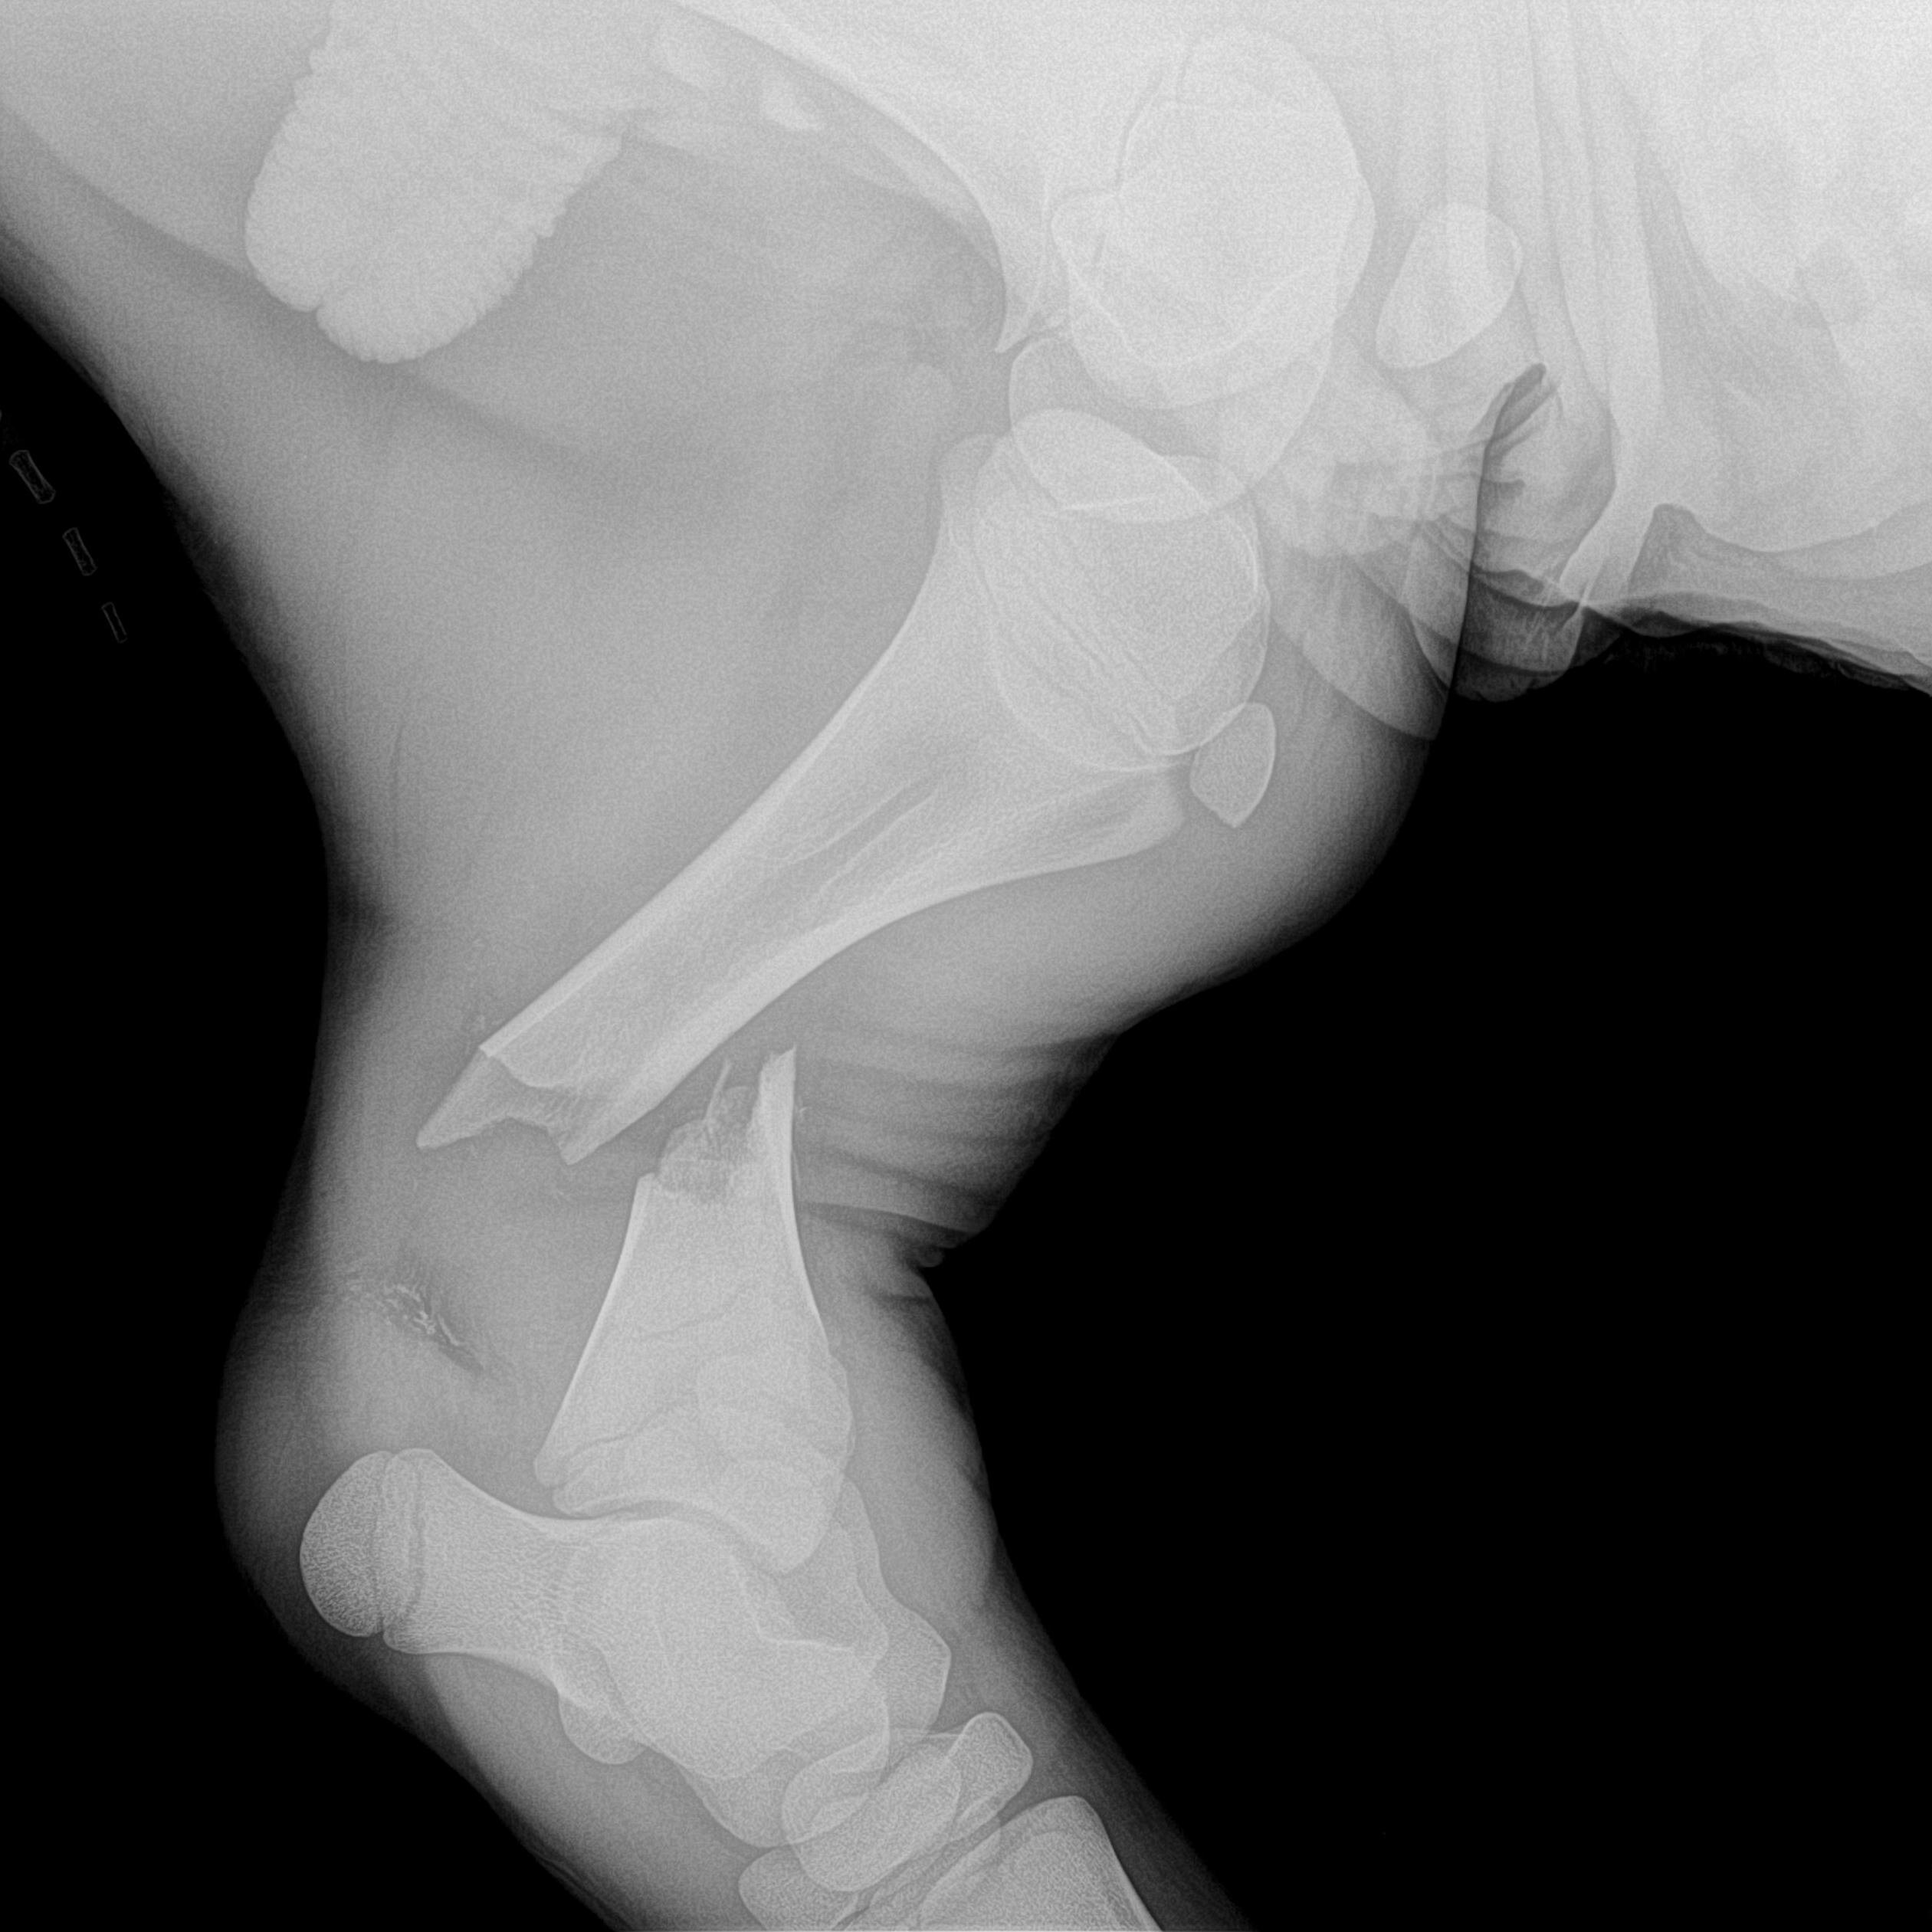

Imagerie

Les différentes technologies d'imagerie aident aux diagnostics : radiologie, échographie, endoscopie...